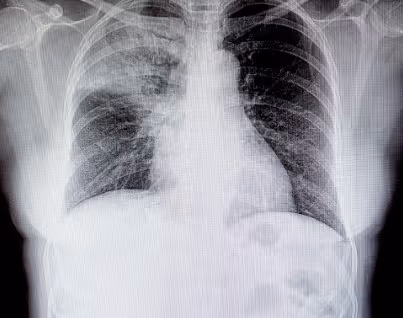

Nem sempre o agente etiológico é possível de identificar com exames, então se liga nessa dica: existem alguns tipos de pneumonia, em que podemos relacionar a anatomia com o agente:

- Lobar ou típica (mais cai em provas e na prática). Principal agente aqui é o Streptococcus pneumoniae (exceto em RN).

Diagnóstico de Pneumonia

Sobre o diagnóstico de pneumonia o Ministério da Saúde tem adotado que seja feito por síndromes clínicas (sinais e sintomas clínicos), tendo como principais sinais para suspeitar: tosse e/ou dispneia.